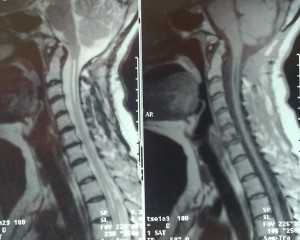

- экстрамедуллярные опухоли могут быть экстрадуральными (располагаются над твёрдой мозговой оболочкой) и интрадуральными, или субдуральными (локализуются под твёрдой мозговой оболочкой).

По гистологической характеристике [1] [8] :

- менингиома (из клеток оболочек головного и спинного мозга);

- невринома (из клеток, образующих миелиновую оболочку нервов);